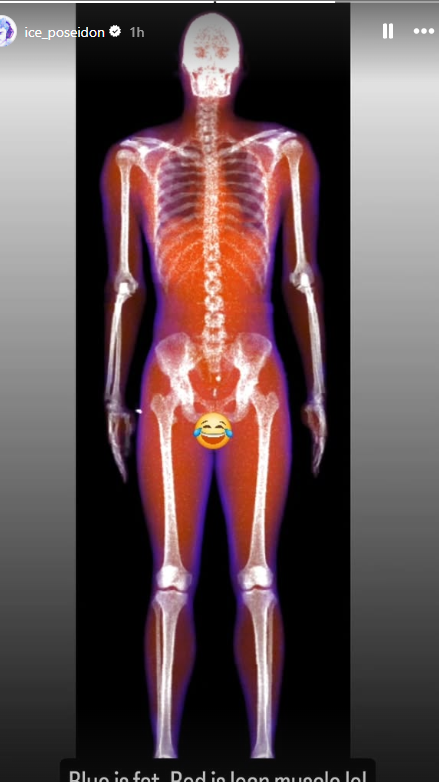

- biacromial is wider than his iliac crests which is ideal

- costal cartilage max is effectively 1:1 with his iliac crest width (ratio of 1 or greater is ideal)

- upward oriented clavicles (not ideal - straight is better but there are some advantages of upward clavicles such as longer deltoid insertions on avg)

now lets morph him to an ideal skeleton

so basically if you look like the morph u should gymmaxx, otherwise, GTFO!